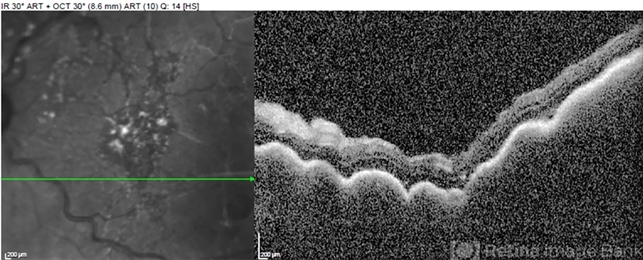

- Uveal lymphoma

- Optical coherence tomography system

- OCT of a 71-year-old man with uveal marginal zone lymphoma shows characteristic "seasick" undulations with replacement of the choroid.